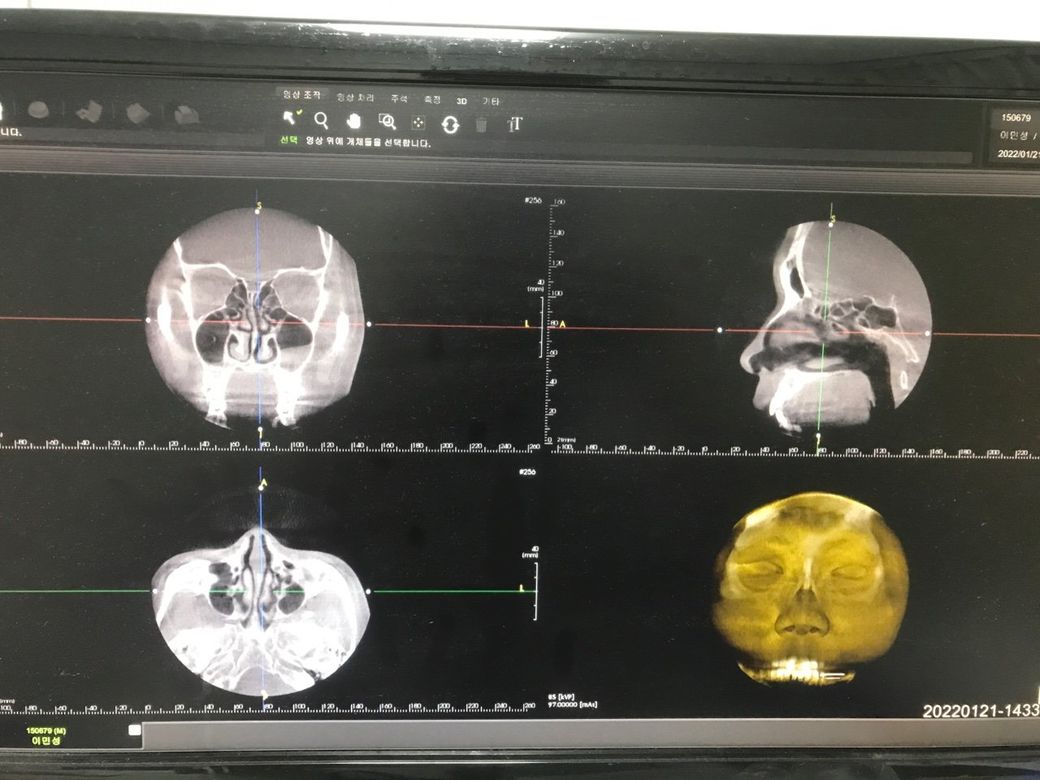

코 ct사진을 찍었는데 판독 부탁 드려도 될까요?

현재 역류성 후두염 으로 진단 받았습니다. 역류성 식도염은 없습니다. 코에 문제가 있어 후두에 자극을 줘 후두염이 올 수있나요? 코 세척 매일 하지만 맑은 콧물이 나옵니다. 자고 일어나면 살짝 누렇게 가래 비슷이 점액질 처럼 뱉어지고 그 후 뱉으면 투명한 점액질 처럼 뱉어집니다

왼쪽 부비동염이 있습니다. 축농증이라고 보통 알고 계시지요. 목에 자극이 있는 증상의 원인이 역류성 식도염일 수도 있지만 부비동염과 동반된 후비루 증후군일 가능성도 높아 보입니다.

• CT는 검사 부위를 여러가지 단면개의 단면으로 촬영하여서 정밀하게 보는 검사이며 질문자님께서 올리신 사진 한 장으로 평가를 할 수 없습니다. 하지만 올리신 CT 사진 컷에서는 매우 정상으로 보입니다.